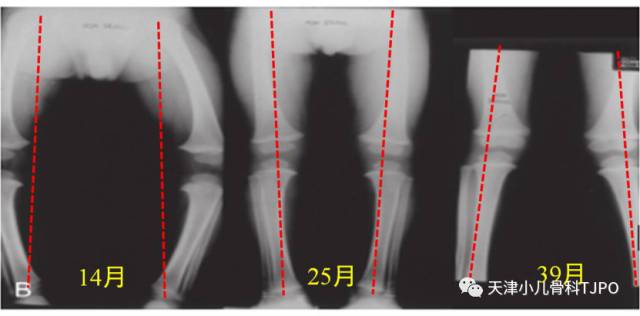

而下面这幅图是教科书上同一个孩子在不同年龄时拍的双下肢的 X线片,从 X线片上很明显能看出"生理性膝内翻"及"生理性膝外翻"的过程。